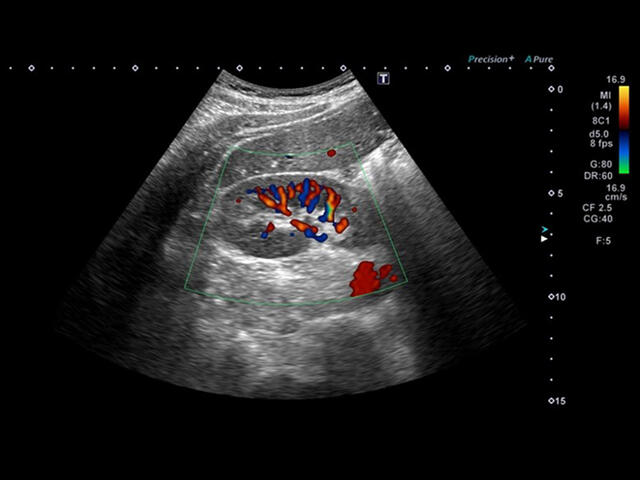

- SMI. Опция, упрощающая визуализацию микроциркуляторного русла. С ее помощью обследуются сосуды с низкой интенсивностью кровотока, изучаются наиболее тонкие структуры. SMI упрощает диагностику новообразований, минимизирует вероятность ошибки.

Уровень сосудистой визуализации SMI в сочетании с высокой частотой кадров повышает диагностическую достоверность при оценке поражений, кист и опухолей.

SMI с цветовой кодировкой позволяет одновременно отображать информацию о потоках и оттенках серого с высокой временной и пространственной информацией.